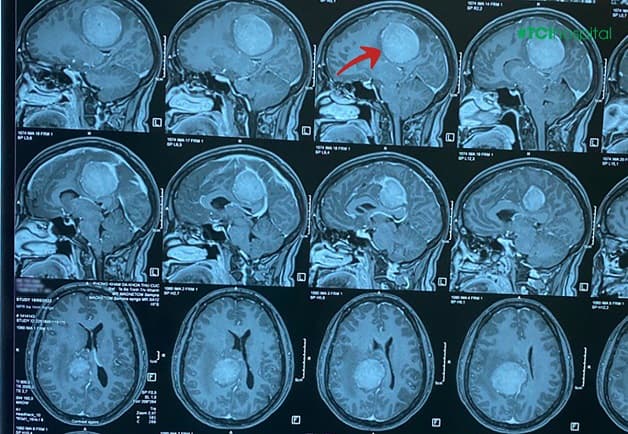

Bệnh nhân Đ.T.V (nữ, 47 tuổi) đã đến Hệ thống Y tế Thu Cúc TCI thăm khám với biểu hiện: đau đầu kéo dài khoảng 2 tháng, cơn đau âm ỉ, giật từng cơn dưới da, đau tăng về đêm, buồn nôn, giảm trí nhớ. Sau khi khám với bác sĩ chuyên khoa Nội thần kinh của TCI và chỉ định chụp cộng hưởng từ MRI não (sọ não, mạch não) thì phát hiện chị V. có khối u màng não kích thước lớn “to như quả trứng” “núp” trong não bệnh nhân.

– Khối u có kích thước ~ 48x46x44mm.

– Quầng phù não quanh tổn thương tương đối rộng, đè đẩy đường giữa cùng hệ thống não thất sang bên trái ~9,5mm, đè đẩy thân thể chai xuống dưới.

– Sau tiêm thuốc đối quang từ, khối ngấm thuốc mạnh và tương đối đồng nhất.

Hình ảnh u màng não dốc nền xoang bướm bên phải trên phim chụp MRI của bệnh nhân N.T.T.D tại Thu Cúc TCI.